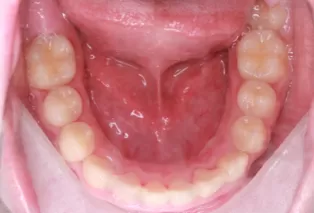

Intraoral photos after treatment